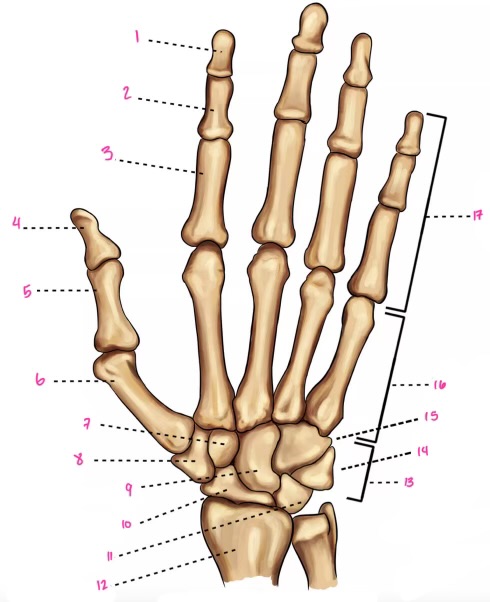

1

1

2

2

3

3

4

9

5

10

6

11

7

14

8

15

9

16

10

17

11

18

1

13

2

14

3

15

4

16

5

17

6

18

7

19

8

20

9

7

22

8

23

9

24

10

25

11

26

13

27

14

28

15

29

16

30

17